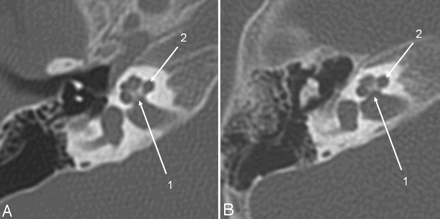

Axial CT section of the right temporal bone obtained with a CTDIvol of 63 mGy (A) (14-month-old patient; DLP, 223 mGy cm; estimated Deff, 1.4 mSv) and with the low-dose protocol (B) (16-month-old child; CTDIvol, 10.8 mGy; DLP, 46.9 mGy cm; estimated Deff, 0.35 mSv). Critical structures like the modiolus and the thin bony lamella separating the internal auditory canal from the cochlea (1) and the spiral osseous lamina (2) are delineated well despite the higher image noise.

The same patients as in Fig 2. Oblique axial image, reformatted in the stapes main plane, a high-dose scan (A) versus a low-dose scan (B). The posterior stapes crus (1) and the incudostapedial articulation (2) are identifiable on both scans.